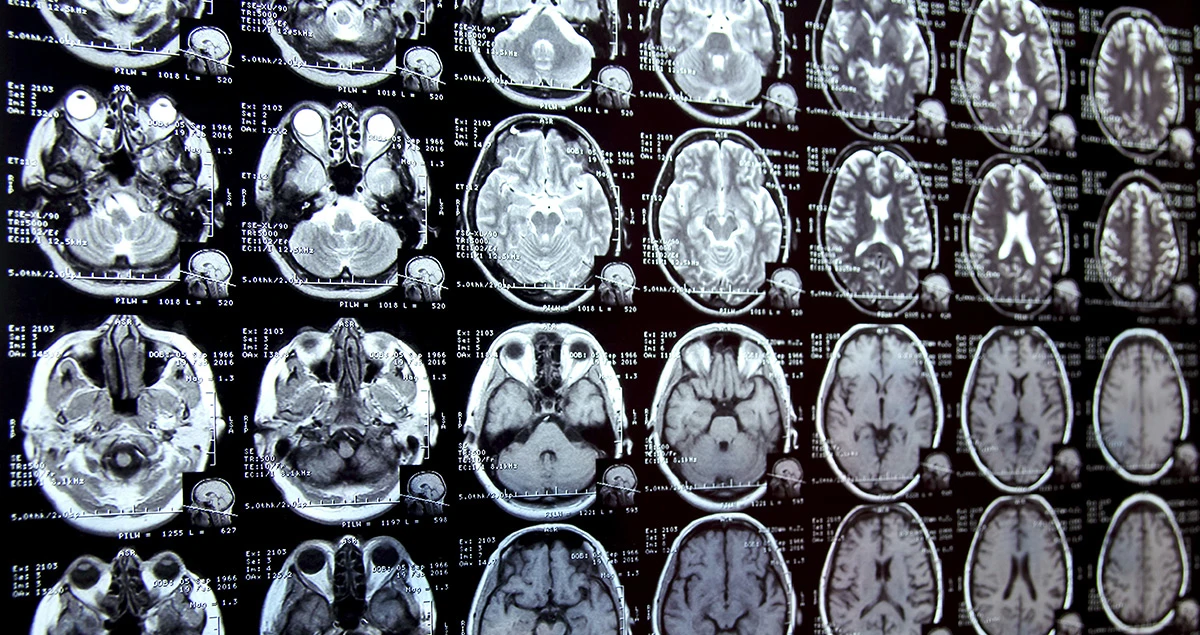

The new device will do the same job as a Magnetic Resonance Imaging (MRI) machine, but Openwater, the start-up, promises it will be cheaper and more accurate. Using infrared light, the handheld gadget can scan five or six inches deep into the body, reporting what it sees to the focus of a micron — the same size as a neuron.

The tool can be used to spot a tumour by detecting the surrounding blood vessels and to see where arteries are clogged. One day, it could follow the flow of oxygenated blood to different areas of the brain, tracking our thoughts and desires.

Researchers have already been able to use MRI to guess what people are looking at. The University of California, Berkeley paid graduate students to lie in MRI machines and watch YouTube videos for hundreds of hours, watching how their brains behaved depending on what they saw.

Then, it showed the students new video clips and was able to roughly replicate the images they saw. Openwater is aiming to show brain activity at a far higher level of detail, down to individual neurons, making this kind of mind-reading more precise. If the company can produce a mass-market consumer product, it would also give neuroscientists far more data for building brain maps.